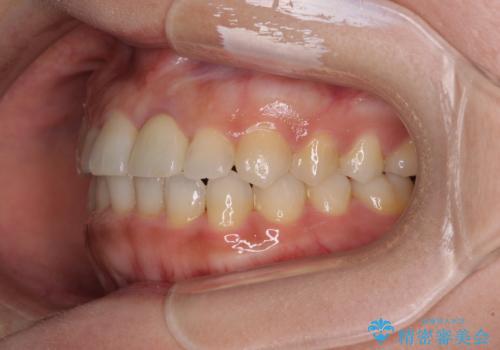

前歯のクロスバイトと変色した歯 ワイヤー矯正とセラミック治療

- 前歯のクロスバイトと神経を取り除いた後に変色してしまった前歯を気にして来院された患者様です。

ワイヤー矯正により矯正治療を行った後に、前歯の補綴治療を行うこととしました。